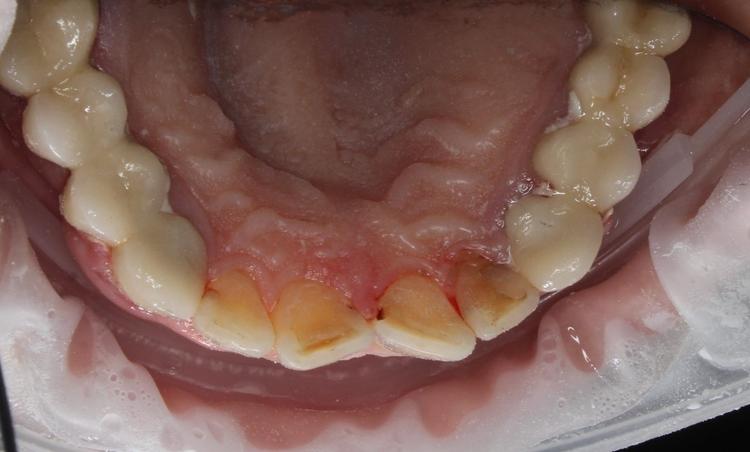

Профессиональная гигиена нижней фронтальной группы зубов

Во время процедуры удален пигментированный зубной налет и камень, проведена полировка зубов.